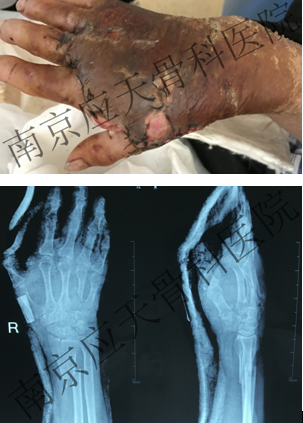

患者安徽池州居民,于2019年11月份不慎挤压致右手疼痛肿胀伴有出血,就诊当地医院,行"清创缝合"处理,术后予以抗感染补液等对症处理,术后切口肿胀伴淡黄色液体渗出,患者为求进一步诊治来我院就诊。

术前: